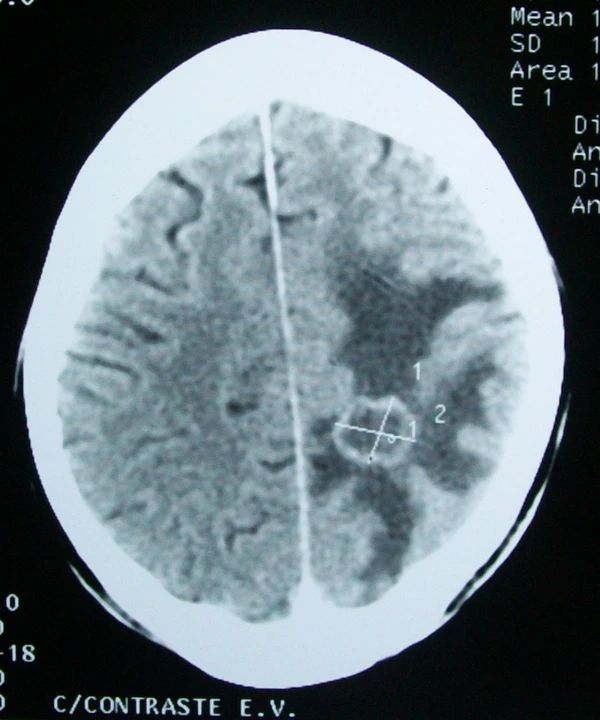

Диагностика

До появления методов визуализации — КТ и МРТ — наличие отека головного мозга постулировалось. Методами его исследования являлись: оценка клинических проявлений, лабораторные методы (динамика электролитного и белкового баланса и др.), инструментальные (ЭЭГ, реоэнцефалография, радиоизотопные) и патологоанатомические исследования (световая, электронная микроскопия и гистохимический анализ)[12]